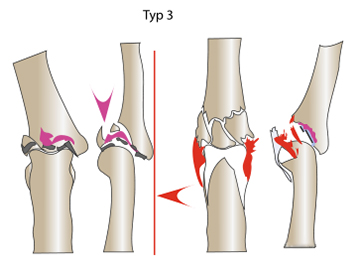

ТИП 3 Опорная суставная поверхность на ладонной стороне разрушена и вся суставная поверхность сдавлена. Отделение костных фрагментов, прикрепленных к связкам (красный).